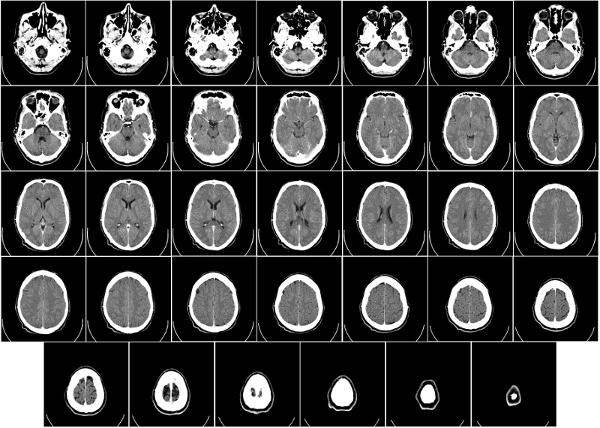

Tomograf a computacional (TC)

(ID 1730)

Resultado de la tomograf a computacional

(ID 2006)

Problema matem tico

(ID 2004)

Soluci n de Hundsfield

(ID 2003)

Soluci n del problema matem tico

(ID 2005)